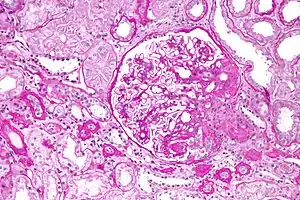

On histology, FSGS manifests as scarring (sclerosis) to segments of glomeruli; moreover, only a portion of glomeruli are affected.[7][20][21] The focal and segmental nature of disease seen on histology help to distinguish FSGS from other types of glomerular sclerosis.[21]

Diagnosis of FSGS is made by renal biopsy that includes at least fifteen serial cuts with at least eight glomeruli.[31][32] Histologic features include sclerosis (scarring) of a portion (average: 15%) of the glomerular space, with only a portion of glomeruli manifesting any sclerosis.[32]

Five mutually exclusive variants of focal segmental glomerulosclerosis may be distinguished by the pathologic findings seen on renal biopsy:[34]